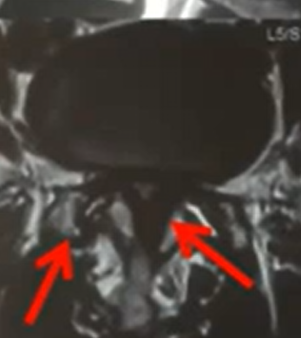

What is Decompression for Lumbar Stenosis?

A surgery to remove thickened ligaments or extra bone pressing on nerves in the lower back, creating more space for nerves.

Laminectomy or Laminotomy

Through a small incision, the surgeon removes bone or ligament pressing on nerves.